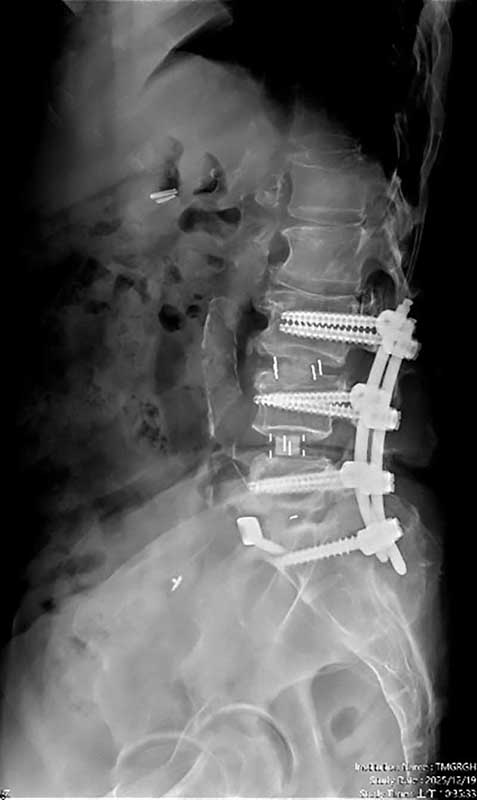

一名65歲婦人,長期飽受腰痛、下肢痠麻及坐骨神經痛困擾,行走距離逐年縮短,嚴重影響日常生活。過去曾接受膝關節保膝手術及脊椎內視鏡減壓治療,初期恢復良好,但因仍存在多節段腰椎退化性狹窄與骨刺問題,加上彎腰負重與久坐習慣未能完全改善,症狀逐漸惡化,甚至出現神經性跛行。經臺中市立老人復健綜合醫院骨科部副部長林琮凱醫師詳細檢查後,診斷為第三、四、五腰椎合併第一薦椎多節段脊椎狹窄與神經壓迫。醫療團隊與病患及家屬充分溝通後,決定採用電腦導航輔助之前位/前側位脊椎融合手術,合併後方骨釘固定,一次完成多節段重建。術後病患神經症狀明顯改善,恢復行走能力,生活品質大幅提升。

相較於傳統脊椎手術需分部位分階段進行、住院與復原時間長,中醫大市醫引進的前位或前側位脊椎融合手術,搭配 3D 電腦導航系統,可在同一次手術中完成多節段融合與多部位重建。手術採間接減壓方式,不需直接進入脊椎腔,大幅降低神經損傷風險。多數病患可於手術當日或隔日配戴背架下床行走,疼痛較少、恢復期明顯縮短,同時提升醫療效能與病患滿意度。